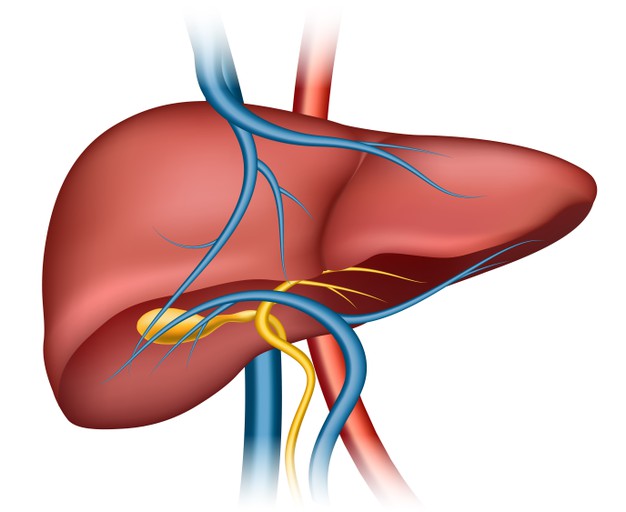

World Liver Day 2024 : लिवर हमारे शरीर का एक बेहद अहम हिस्सा है, जो कई जरूरी फंक्शन करता है, जहां यह ऑर्गन और ग्लैंड दोनों की तरह काम करता है। वहीं इसके महत्वपूर्ण फंक्शन्स में बॉडी डिटॉक्सीफिकेशन, बाइल जूस बनाना, प्रोटीन और फैट के मेटाबॉलिज्म में मदद करना, एनर्जी स्टोर करने जैसे काम शामिल हैं।